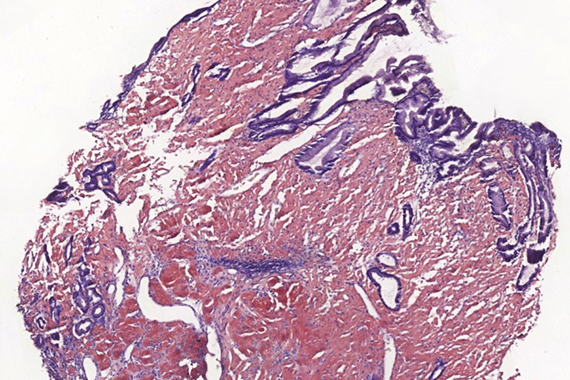

Biopsy and resection of stomach from a 45-year-old male with suspected gastric cancer.

Localized gastric amyloidosis.

Histologically, lamina propria of gastric mucosa was expanded with amorphous paucicellular stromal deposits with cracking artifacts (Panels A and B). These depositions stained red with Congo Red stain (Panel C) and demonstrated characteristic apple-green birefringence in polarized light (Panel D). No malignancy was observed. Consequently, the final diagnosis was gastric amyloidosis.

Due to recurrent gastrointestinal bleeding and significant involvement of the stomach with amyloidosis, a distal resection of stomach was performed. Histological findings (Panel E) in the resection specimen, including Congo Red stain (Panel F) were similar to those described in the pre-operative biopsy.